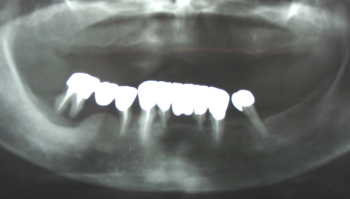

上顎は1本も歯がない状態

下顎も歯槽膿漏(しそうのうろう)でぐらぐらの状態です。

上顎にインプラント(人工歯根)を植えました。

右奥の歯は歯槽膿漏がひどいので抜きました。